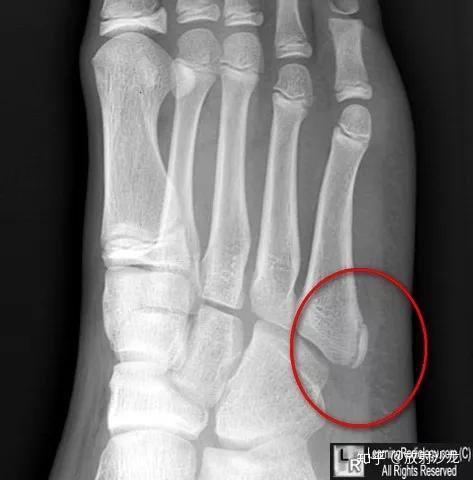

正常儿童骨骼解剖 -右第五跖骨基底部骨骺误为骨折

副骨骺(accessory epiphysis).